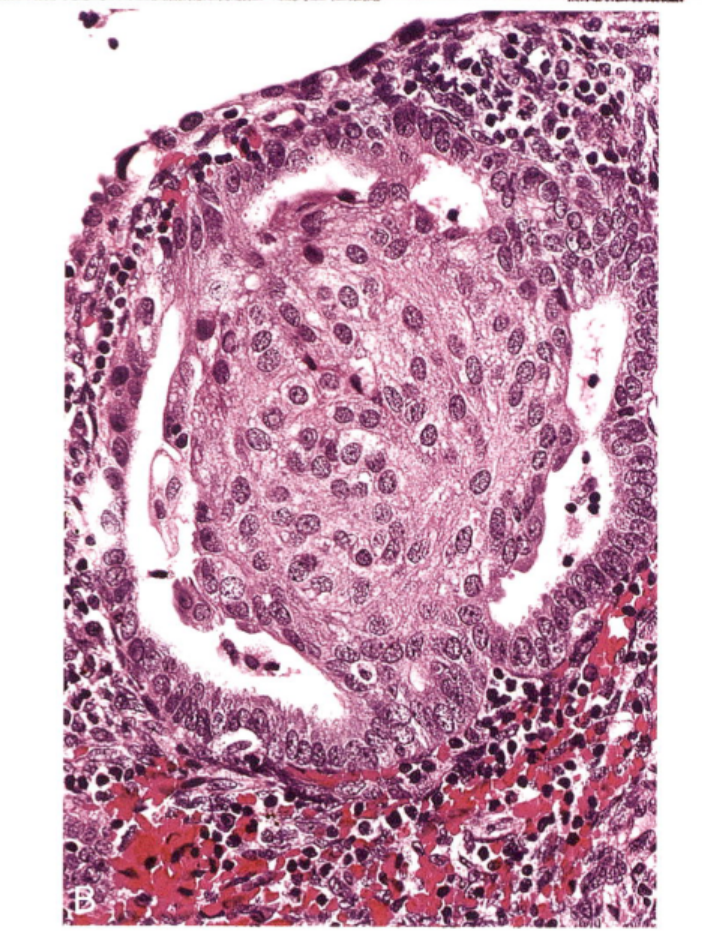

·乳头状合体细胞化生

嗜酸性细胞沿表面上皮聚集成合体细胞和乳头状结构,常见于子宫内膜崩解